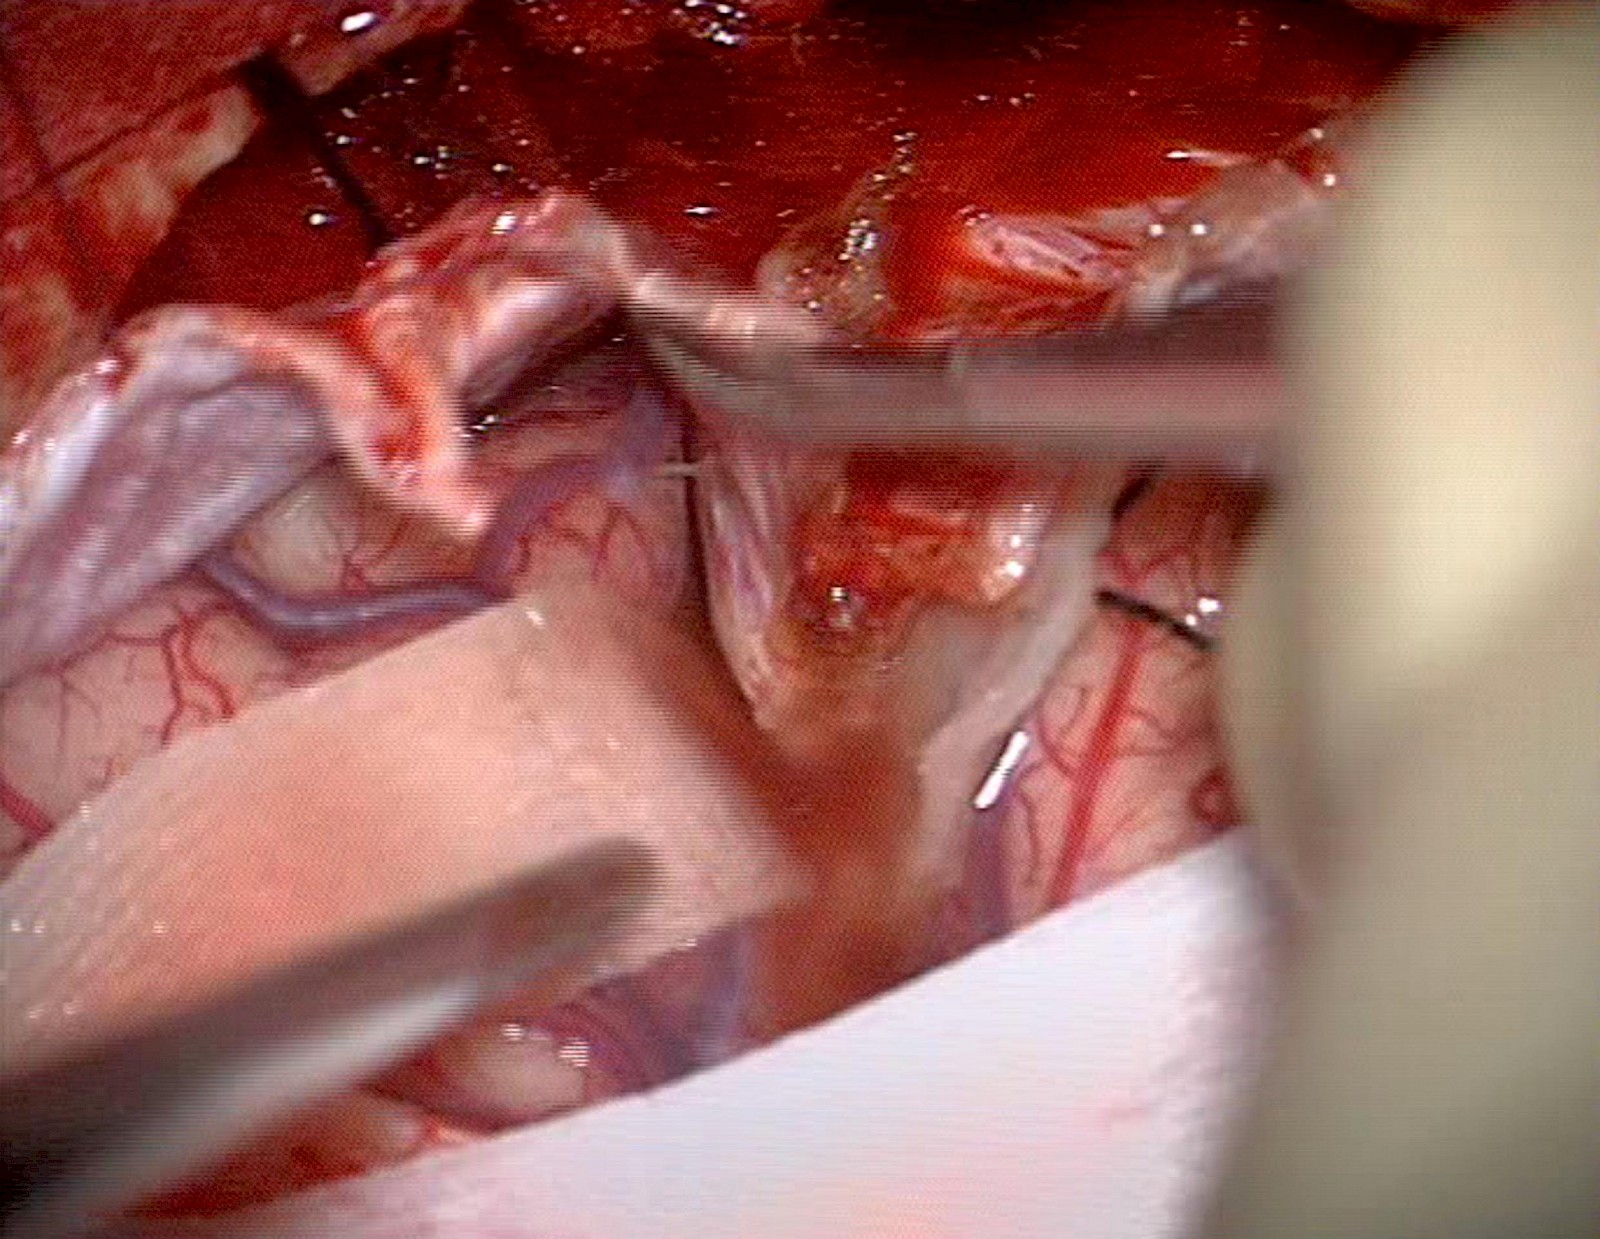

Entwickelt und geforscht wird von mir an digitalen 3D-Modellen des Hirnstamms und dessen umliegenden Strukturen. Diese sind interaktiv nutzbar und ab Herbst von Chirurgen als individuelle Patientendaten über eine OP-Navigations-Applikation einsetzbar.

Die dreidimensionalen Hirn-Strukturen werden über den gezielten Einsatz verschiedener Medien entwickelt, basierend auf den bildgebenden Verfahren MRT und CT. Die MRT-Datensätze besitzen ein bestimmtes Format, das nicht direkt bearbeitbar ist. Diese Daten verarbeite ich anfangs selektiv, erst nach diesem Prozess sind diese direkt gestaltbar. Die 3D-OP-Situs Prototyp-Applikation unterstützt die präoperative Planung und leistet Wissensvermittlung an Fachpersonal. Dies erweitert das Sichtfeld während der Operation und das räumliche Verständnis des Chirurgen. Die medizinischen Daten und der OP-Situs werden interaktiv erfahrbar. Dieser Prozess lässt die abstrakten medizinischen Daten im Raum und in Farbe erscheinen.